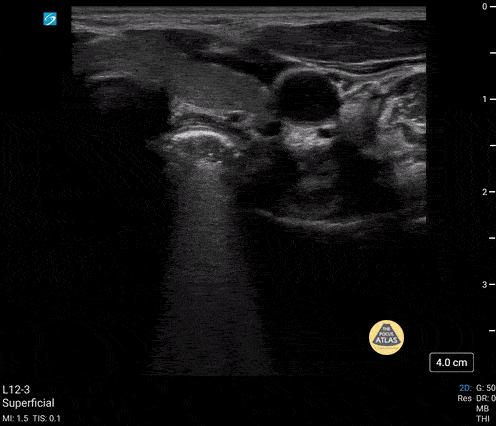

5 yo male presents with swallowed decorative marble. no difficulty breathing. unable to handle secretions. POCUS shows an esophageal FB that was later removed by surgery. Contributor: Paul Khalil, MD Nicklaus Children's Hospital, @khalil3paul